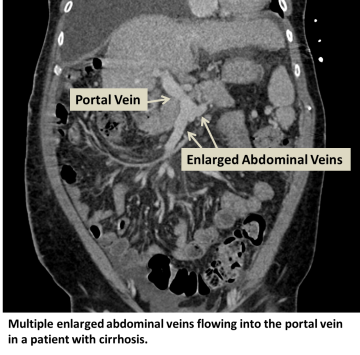

Portal hypertension is increased blood pressure in the portal venous system, a system of veins draining the abdominal organs into the portal vein, which then drains into the liver. Portal hypertension can result in blood backing up into various abdominal organs, such as the spleen, esophagus, and rectum with resultant bleeding.

Portal hypertension can be caused by anything that limits blood flow through the portal vein, through the hepatic veins draining the liver, or through the liver itself. As a result, pressure builds up in the portal system. Examples of conditions that can cause portal hypertension include portal vein clots, liver disease, and right heart failure. The most common cause of portal hypertension is chronic liver scarring called cirrhosis.